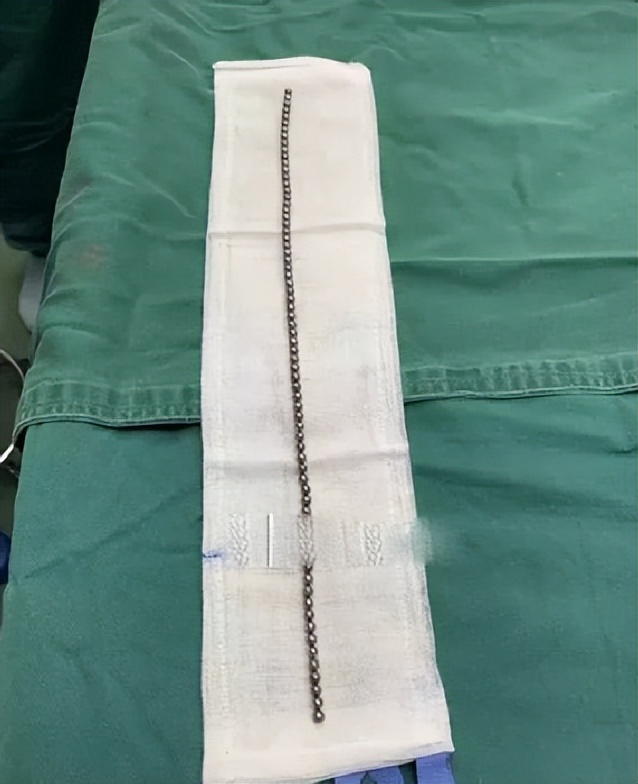

这些珠子连在一起长达10公分左右,又因为有磁性,医生最后通过手术切开小口才将珠子取出来。

去年,广东一名13岁男孩往尿道里塞进186颗磁力珠!

去医院检查后发现那么多的磁力球全都粘在一起无法排出,医生只能靠手术一颗颗夹出来。